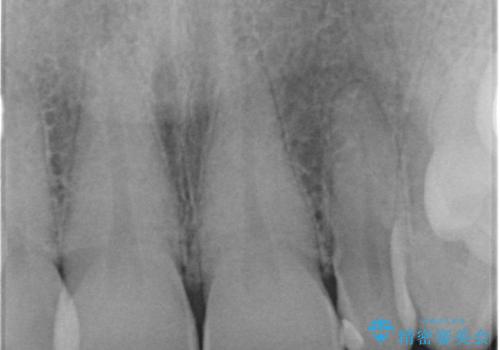

歯の向きは悪くなかったため、神経は取らずに治療しました。